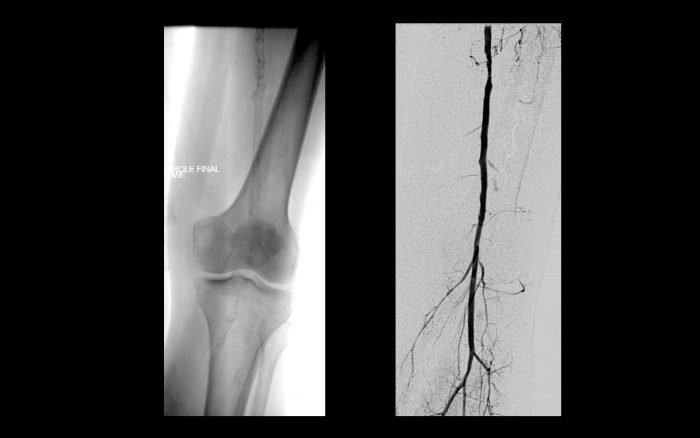

Após cerca de 1 ano, o paciente evolui com claudicação intermitente para curtas distâncias predominando do membro inferior direito.